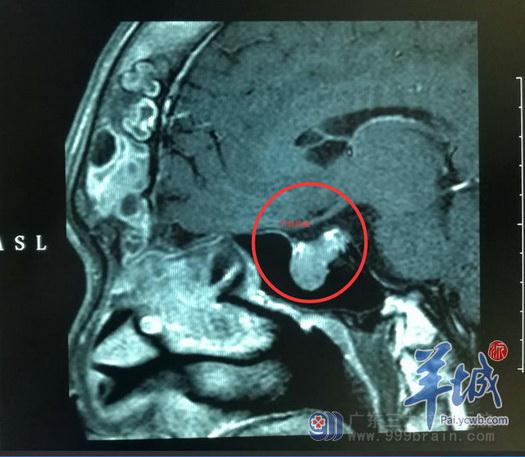

二十多年来,他因垂体瘤导致头颅变长、嘴唇肥厚、手脚粗大、脊柱变形,严重影响了工作和生活。近日在广东三九脑科医院,医生通过经鼻蝶垂体瘤切除术,顺利为其切除肿瘤。

3月,他前往广东三九脑科医院就医。完善相关检查后,医生考虑垂体瘤复发,建议手术治疗。但邓均的父母依旧十分担心,邓均也因此犹豫不决。

3月底,他终于下定决心手术。3月29日,广东三九脑科医院神经外五科主任鲁明为其在全麻下行内镜下经鼻蝶垂体瘤切除术。

与传统开颅手术不同的是,这次采取的是手术创伤相对较小的经鼻蝶入路方式。鲁明主任在神经内镜和导航定位下,通过鼻腔,将复杂的垂体瘤全切除。术中对脑垂体、视神经、颈内动脉等保护完好。